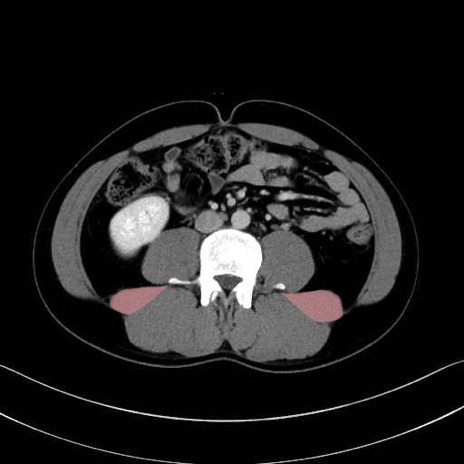

腰方形筋 (Quadratus lumborum)